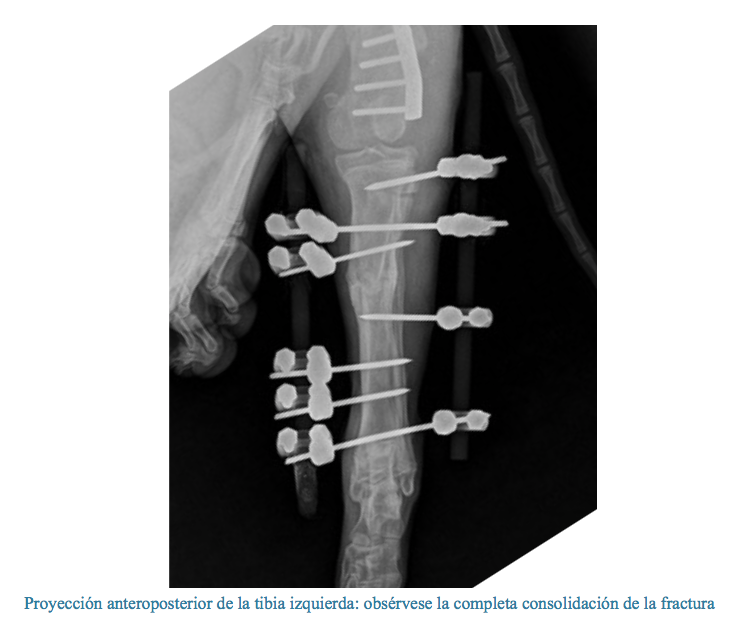

Fractura diafisaria de tibia tratada con fijación externa